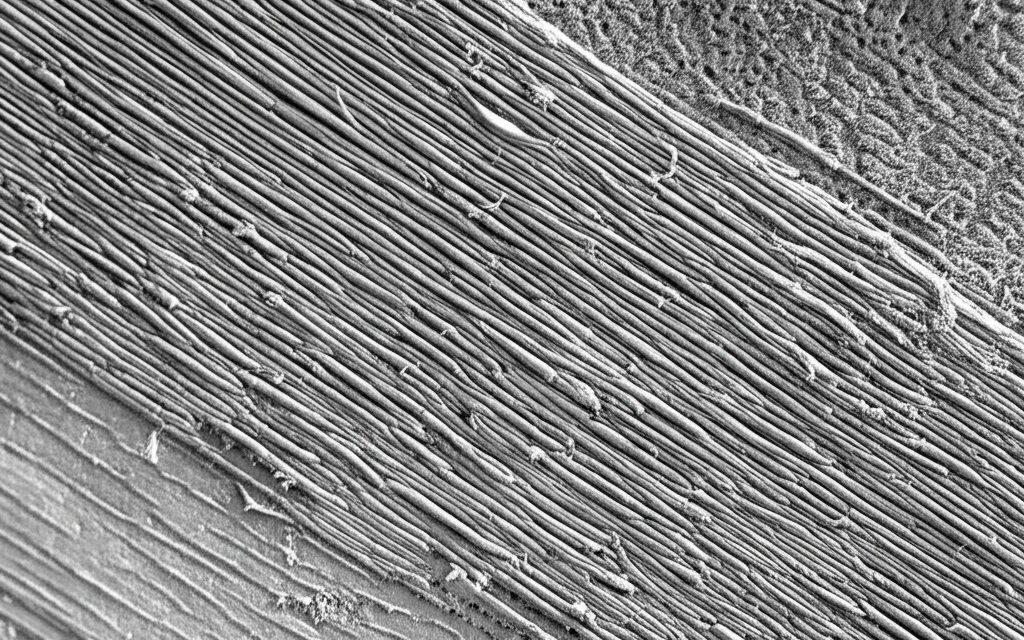

Un Cristallino Diverso: Ordine e Compattazione nella Miopia Elevata

La prima cosa che ci ha colpito osservando i cristallini di pazienti con miopia elevata e cataratta (che chiameremo HMC, Highly Myopic Cataracts) è stata la loro struttura. A differenza della cataratta senile comune (ARC, Age-Related Cataracts), dove le fibre del cristallino nella parte esterna (corteccia) appaiono disordinate, nei pazienti HMC abbiamo notato un’organizzazione quasi maniacale: le fibre erano allineate in modo polarizzato e incredibilmente compatto, specialmente nel nucleo, un po’ come gli strati di una cipolla. Questa osservazione ci ha fatto pensare: deve esserci un meccanismo specifico all’opera nella miopia elevata che regola l’allineamento di queste fibre e che, in qualche modo, accelera l’indurimento (sclerosi) del nucleo. Anche le cellule epiteliali del cristallino (LECs) prelevate da questi pazienti mostravano un comportamento diverso in coltura: tendevano a migrare in modo orientato e ad allungarsi, segno di una spiccata polarità cellulare, cosa molto meno evidente nelle cellule da cataratta senile comune.